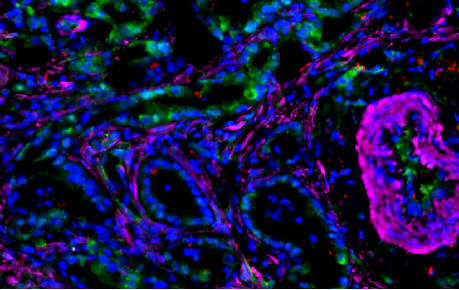

Fluorescence Scanning Features

KFBIO Digital Pathology Slide Scanners (fluorescence) have excellent performance in the accuracy of movement, focus, and image processing, and its accurate whole slide imaging not only meets the requirements of digital slide viewing and operation but is also suitable for AI-assisted image analysis.

Excellent Cross Color Suppression Design

Independent LED light source avoids cross color. High contrast, high brightness, no drift, and no cross color make it more suitable for specific fluorescence channels. Equipped with CHROMA filter narrowband filter, the minimum spectral band resolution reaches 10nm, which can efficiently separates different fluorescence channels to achieve large information density without affecting the quality of data.

High-Sensitivity Cooled Scientific CMOS Camera

Dhyana 400D high-sensitivity refrigeration scientific CMOS camera is equipped, low signal-to-noise ratio and high resolution, with a new 1.2 inch surface array scientific CMOS chip. The quantum efficiency at 600 nm is up to 80%. 6.5 μm pixel size and 2*2 pixel binning function realized by FPGA, suitable for low-light detection and imaging. The Dhyana 400D has excellent performance, with only 2 electrons of readout noise. The browsing speed is up to 35 frames/s at 4 megapixels. And the data transmission speed is up to 5Gb/s to provide strong support for users’ work.

Multiplex immunofluorescence scanning

Tumor micro environment analysis/

spatial transcriptome analysis